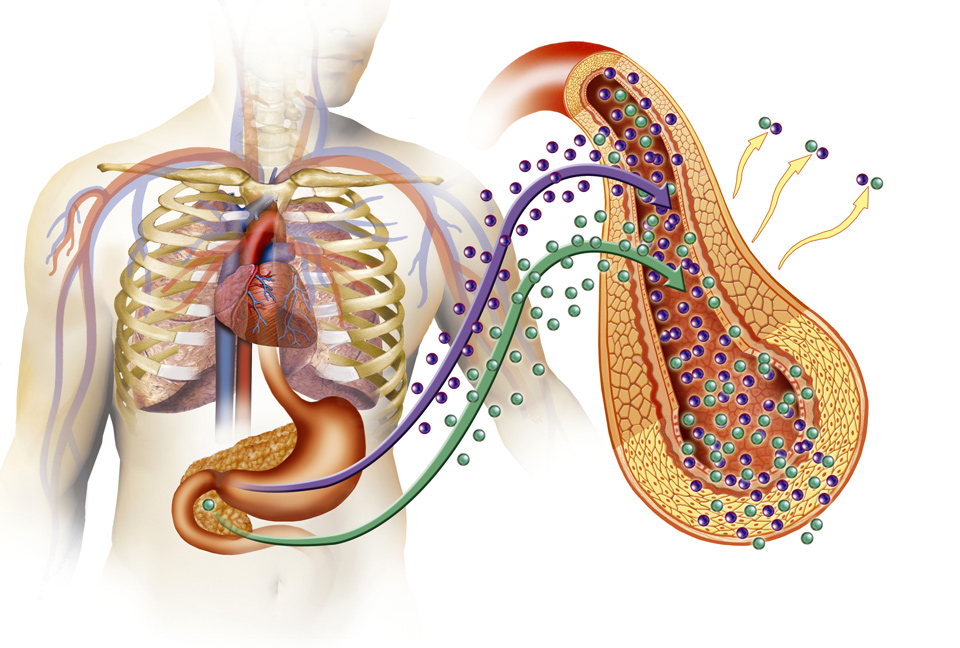

Sobre ello actualmente existen varios estudios en fase experimental, y algunos de ellos han sido publicados en humanos con resultados muy esperanzadores. Basado en los estudios iniciales del Dr Rubino y el Dr Cohen, hemos visto el papel que juega el intestino en la fisiopatología de esta enfermedad. Partiendo de esto último sabemos que al excluir el paso del alimento por determinadas porciones del intestino (duodeno y primeras asas de yeyuno) podemos mejorar la función pancreática, disminuir las cifras de glicemia y curar así esta enfermedad. Esto es posible gracias a la actividad de ciertas hormonas intestinales inducidas por la cirugía.